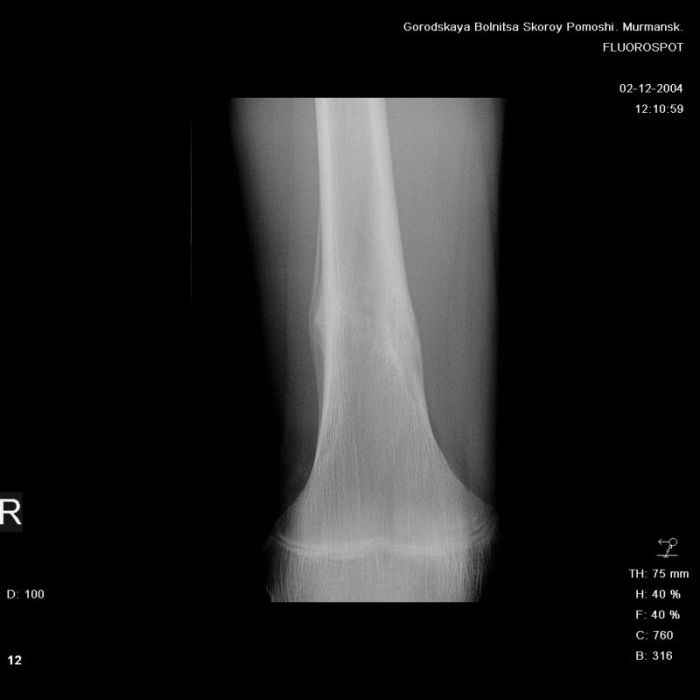

Анамнез практически никакой: в следствие травмы (растяжение связок коленного сустава) от 07.11.2004 выполнены Rg-граммы в травмпункте и обнаружено опухолевидное образование. Первичные Rg-граммы я не публикую, так как они заметно худшего качества, да и динамики за прошедшие три недели не отражают. Болевой синдром купирован в течение трёх дней. В настоящий момент мальчика ничего не беспокоит. Ходьба не нарушена, опухоль пальпируется с трудом по задней поверхности в н\3 правого бедра, пальпация безболезненна, объем движений в суставах правой нижней конечности полный и симметричный. Кожа над опухолью не изменена. В нашей клинике проведено дополнительное обследование: общие анализы крови и мочи, биохимия крови без особенностей. Выполнены Rg-граммы на цифровом Siemens обычные и продольные томограммы срезами 3-5 мм, а также компьютерная томография поперечными срезами по 5 мм. Прошу обратить внимание, что на приведённых томограммах видны две полости 10х15 мм и 15х60 мм. Также имеются два опухолевидных образований наслаивающихся друг на друга: уплощённое и вытянутое 10х100 мм и элипсовидной формы 15х30 мм. Это хорошо заметно на фото a_1.jpg c_1.jpg и d_1.jpg. Плотность внутри полостей 125% от плотности костномозгового канала, плотность наружного опухолевидного образования 55% от плотности кортикального слоя. Также отмечается линия перелома по центру наружного опухолевидного образования. Исходя из полученных данных мнения в плане диагноза несколько разделились от 1)сочетания кортикальной фиброзной дисплазии и латентно протекавшего маршевого перелома н\3 правого бедра до 2)остеосаркомы. В отношении первого варианта не сходится отсутствие клиники при переломе такой крупной кости как бедро, второй вариант вообще оставлю без комментария, ибо некомпетентен. Хотелось бы услышать мнения коллег, с удовольствием ознакомлюсь с любыми предположениями и замечаниями. С уважением, Александр Е. Клоков Отделение детской ортопедии и травматологии БСМП г. Мурманска.